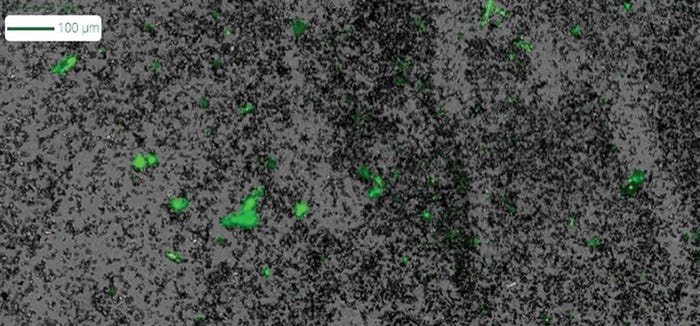

To help address this critical need, we’ve developed Aura® GT; a game-changing technology that provides an easier way to evaluate LNP quality and ensure the success of your drug delivery projects. Aura uses Backgrounded Membrane Imaging (BMI), a contemporary form of membrane microscopy that enables high throughput, low volume subvisible particle characterization.

And, by leveraging SYBR™ Gold assay via Fluorescence Membrane Microscopy (FMM), Aura GT allows you to assess both the stability and purity of samples in high throughput, low volume testing, enabling accurate LNP characterization at earlier stages, from initial development all the way through to final product release.

Aura GT’s SYBR Gold assay characterizes nucleic acid escape in stressed LNP samples and quantitatively analyze the stability and purity of these samples.

The challenges of accurately predicting quality and stability for lipid nanoparticles can be addressed with the help of Aura GT. By measuring LNP quality with as little as 5 μL of sample, Aura GT provides researchers and developers with unprecedented control over their drug delivery process – allowing them to monitor and evaluate subvisible particles with unparalleled accuracy.